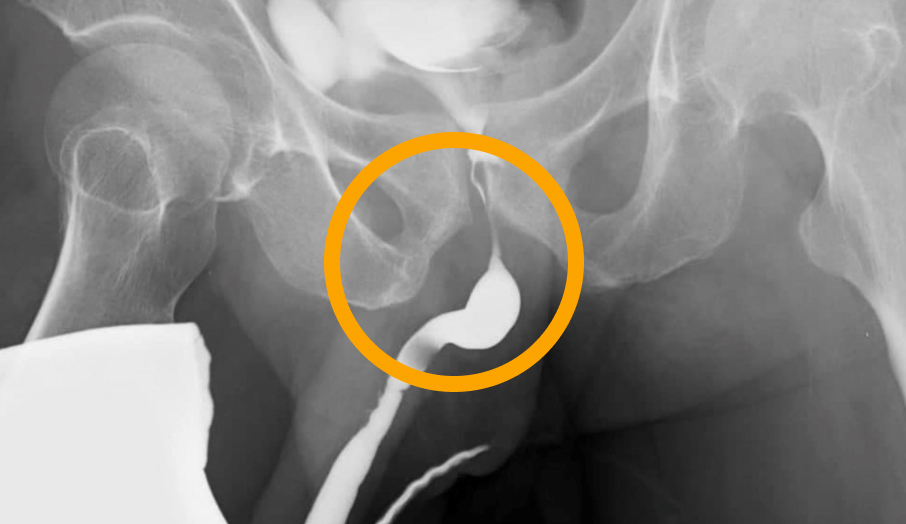

정상 방광

구상화 병변

궤양 병변